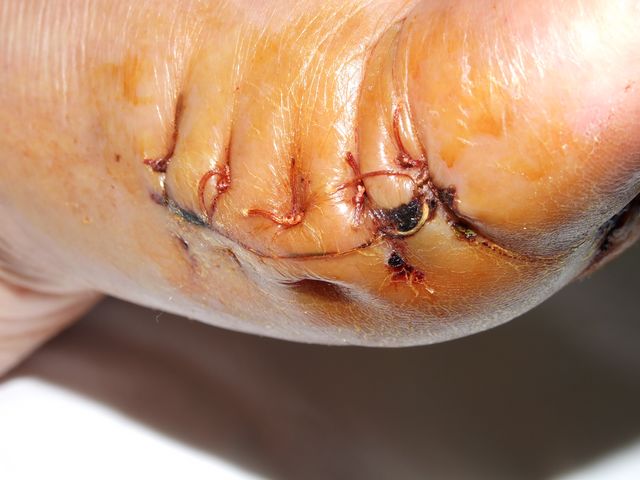

Avulsión quirúrgica